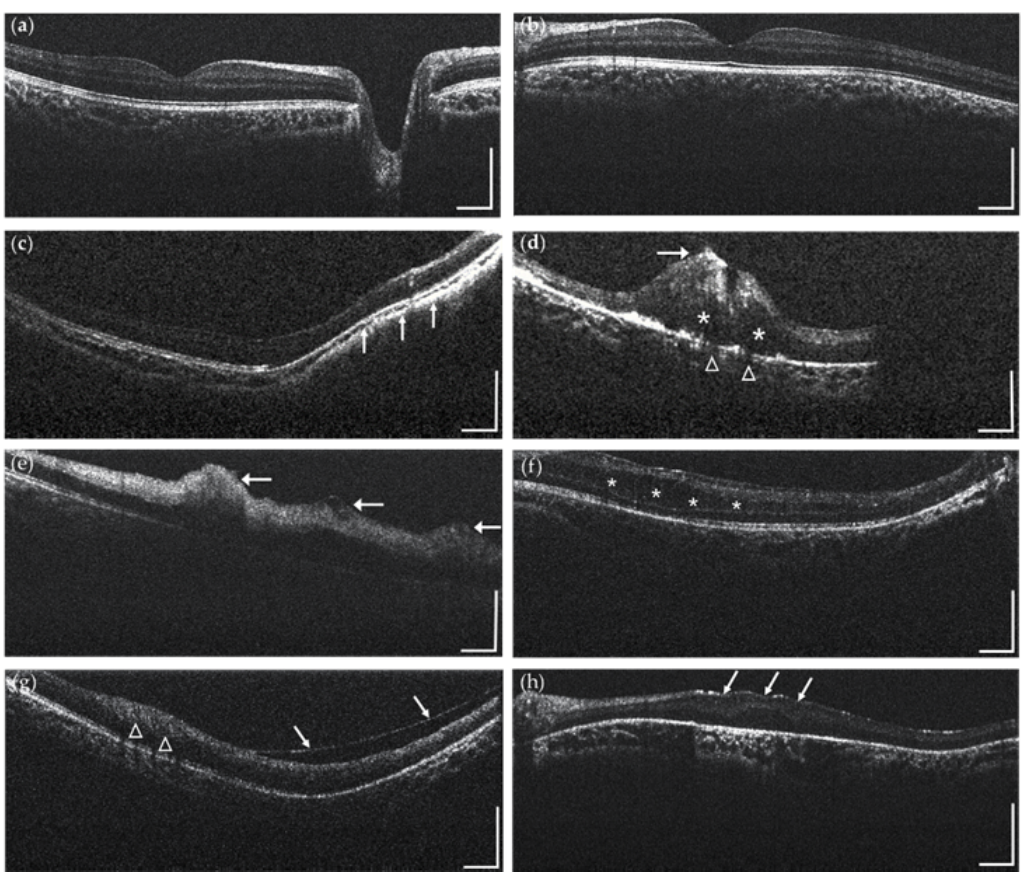

《2025中国OCT操作规范专家共识》发布:为眼底病诊疗提供新指引

近日,《中国眼底OCT操作及图像阅读报告规范德尔菲法专家共识(2025年)》正式发布,为眼底病的诊断和治疗提供了新的指导和规范。这一专家共识的发布,标志着我国在眼底病诊疗领域迈出了重要的一步,为临床医生提供了更加科学、规范的操作指南,也为患者带来了更好的诊疗体验。